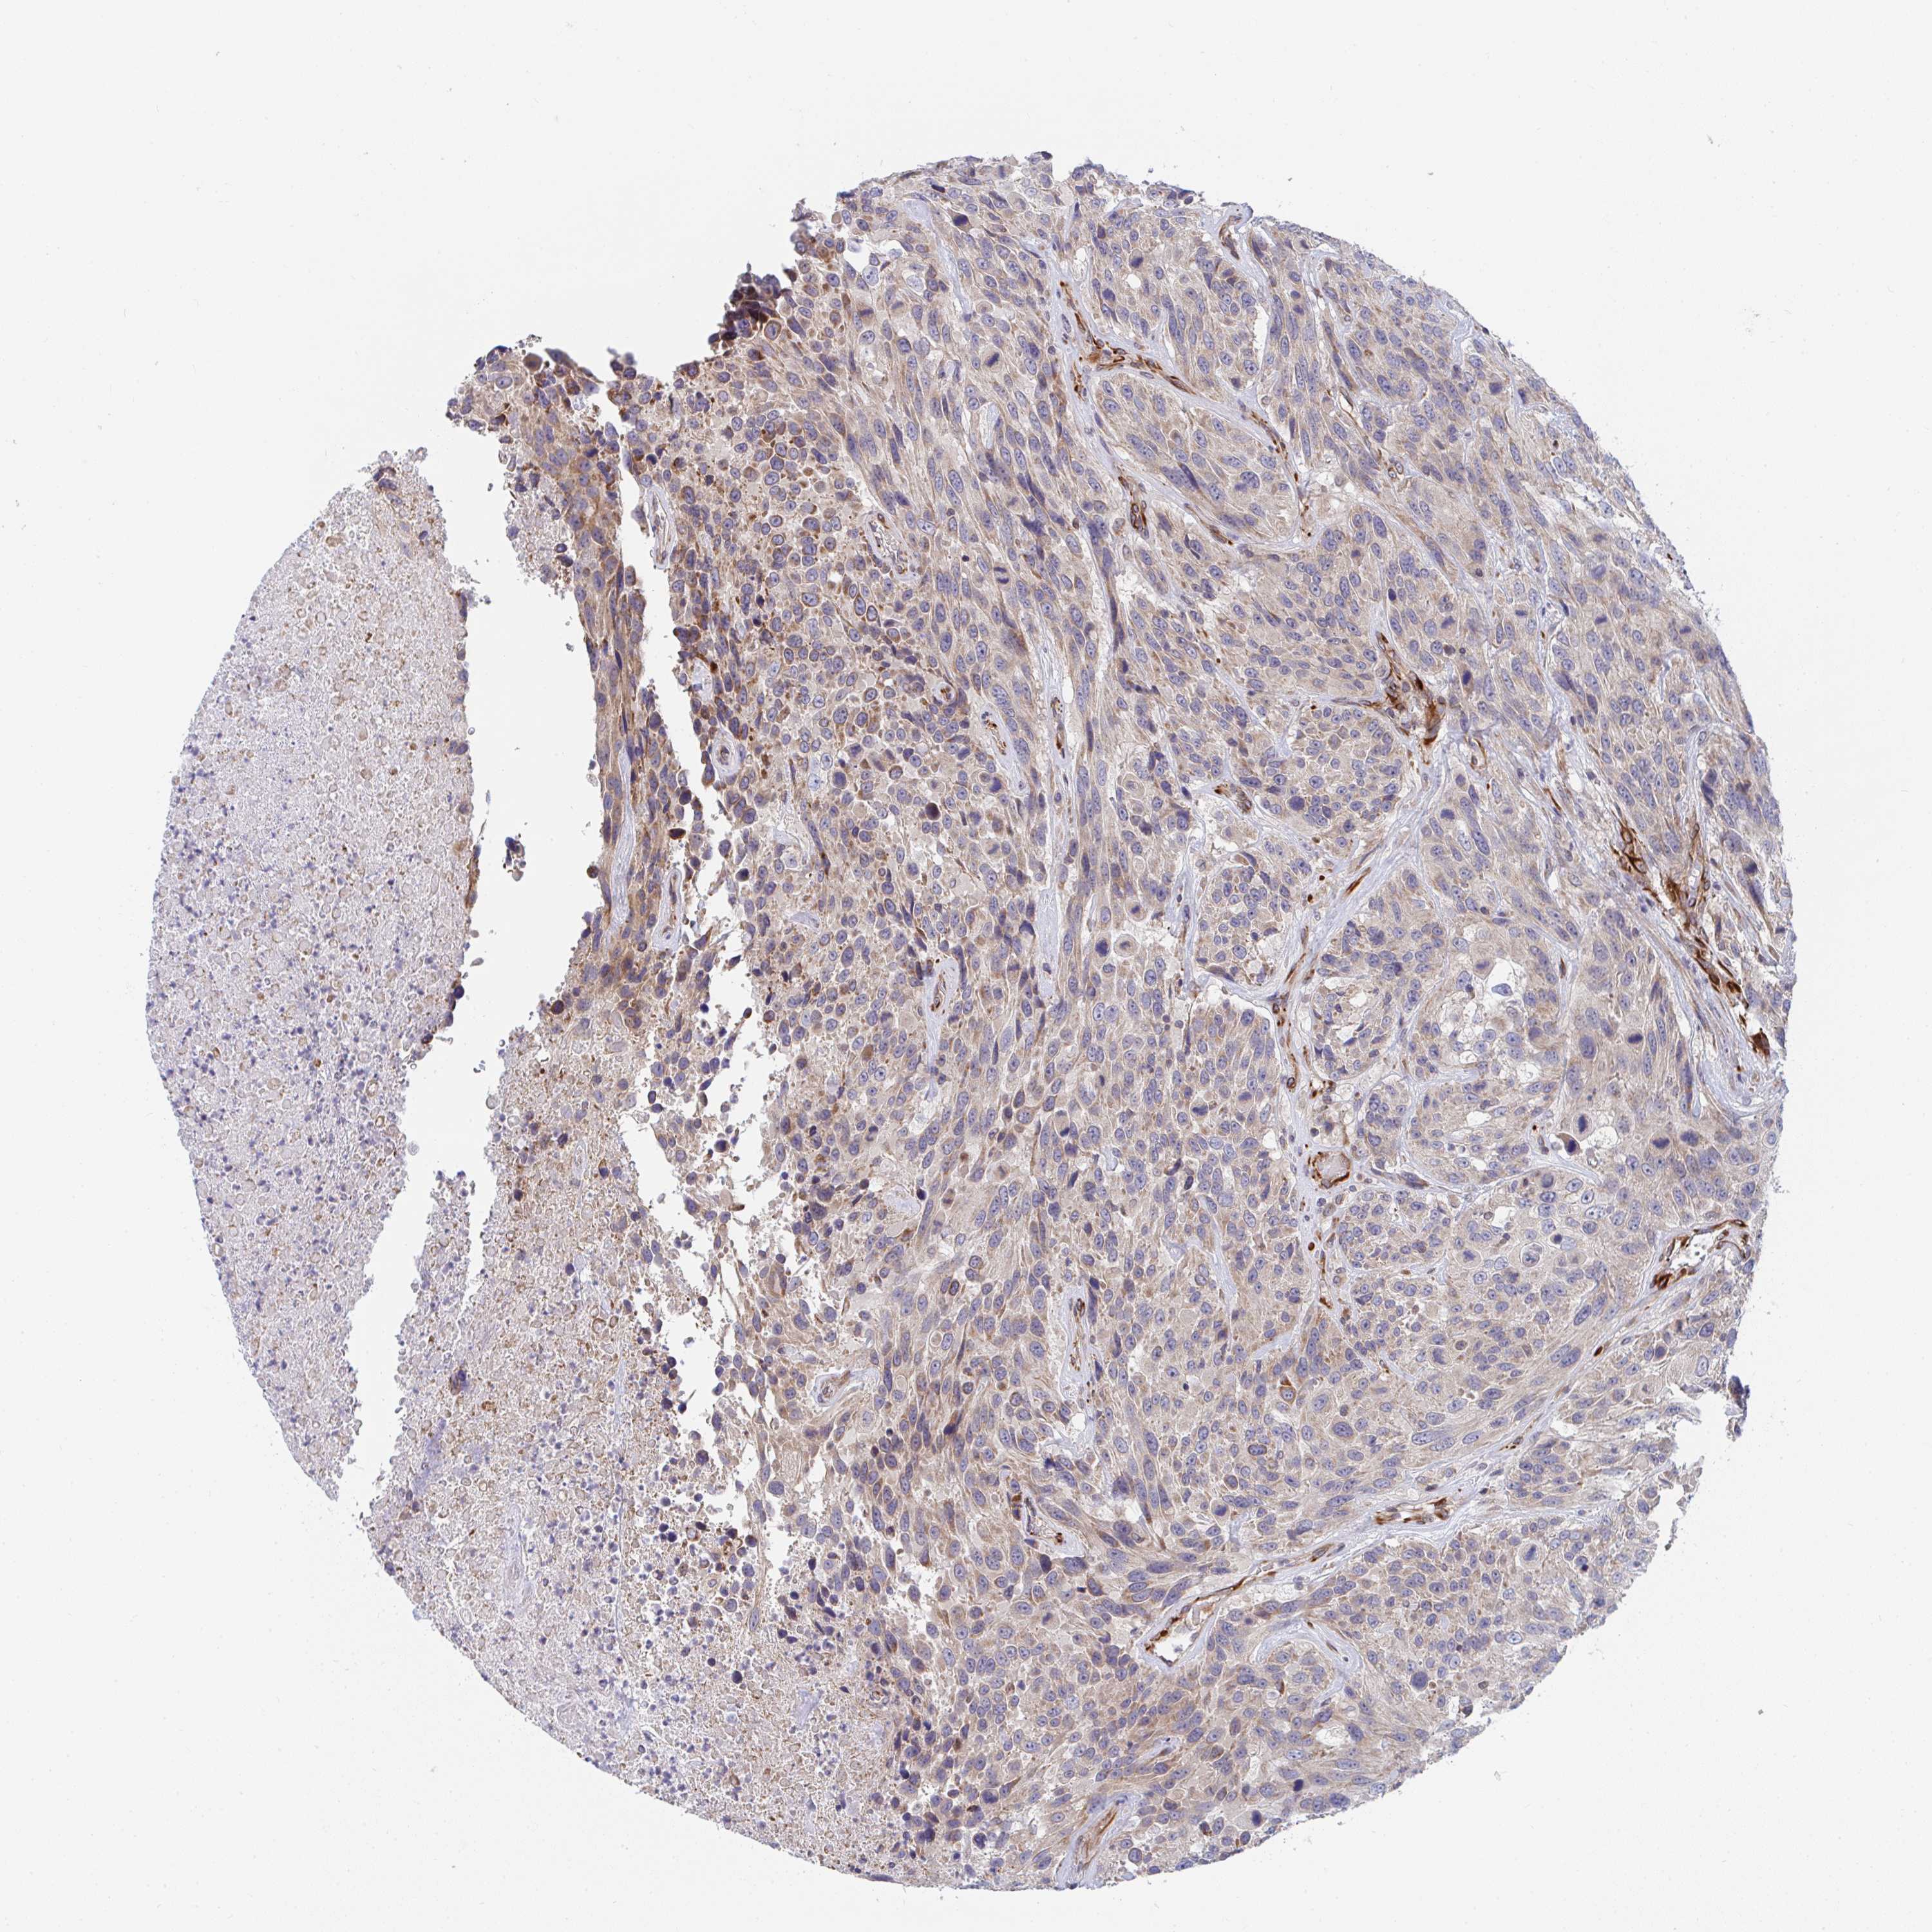

UROTHELIAL CANCER - Protein expressioni

A mouse-over function shows sample information and annotation data. Click on an image to view it in a full screen mode. Samples can be filtered based on level of antibody staining by selecting one or several of the following categories: high, medium, low and not detected. The assay and annotation is described here.

Note that samples used for immunohistochemistry by the Human Protein Atlas do not correspond to samples in the TCGA dataset.

Antibody stainingi

Antibody staining in the annotated cell types in the current human tissue is reported as not detected, low, medium, or high, based on conventional immunohistochemistry profiling in selected tissues. This score is based on the combination of the staining intensity and fraction of stained cells.

Each image is clickable and will lead to virtual microscopy that enables deeper exploration of all samples and also displays staining intensity scores, fraction scores and subcellular localization as well as patient and tissue information for each sample.

Antibody HPA054991

Antibody HPA058735

Urothelial carcinoma, High grade

Urothelial carcinoma, NOS

Urothelial carcinoma, Low grade